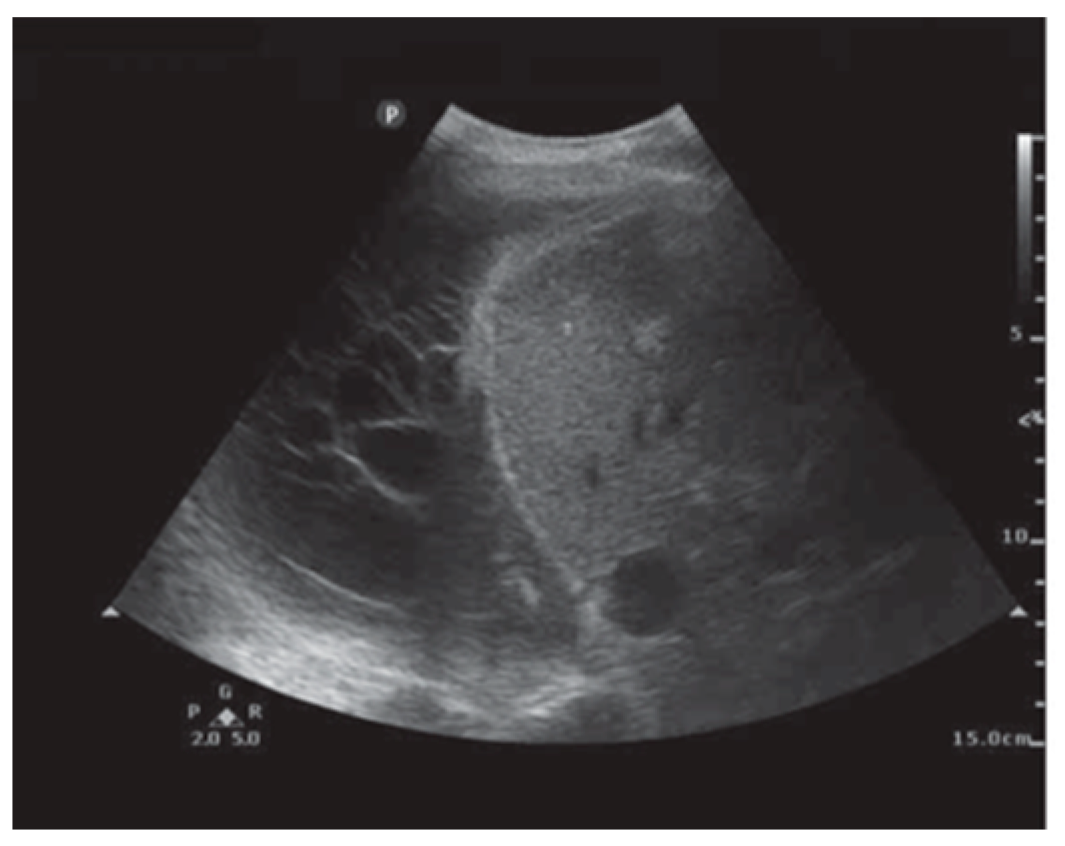

In addition to HRCT, there are several other imaging advancements very similar to the ones discussed in the lung cancer section that help in the diagnosis and monitoring of parenchymal lung diseases, including OCT, ultrasound, and PET. Earlier, we reviewed how OCT can be helpful for diagnosing lung nodules. Similarly, OCT offers minimally invasive high-resolution images for ILD diagnosis [20]. OCT has been shown to have sensitivity and specificity of 100% in detecting usual interstitial pneumonia patterns [21]. External validation and larger studies are required for clinical implementation. This could reduce reliance on surgical lung biopsy. Another form of imaging used includes ultrasound, which we have seen used for lung nodules as well. For parenchymal lung diseases, the pattern of abnormality is typically more diffuse. The radial ultrasound probe is inserted through a bronchoscope into the patient’s airways until it reaches the pleural surface. The probe is then slowly withdrawn from the pleura to the hilum, while examining the characteristics on the ultrasound image. This method helps determine a better location to biopsy. A dense sign correlates with a higher pathological confidence than a blizzard sign (Figure 3). Moreover, radial EBUS helps clinicians choose appropriate biopsy sites for cryobiopsy and identify blood vessels close to lesions, which should be avoided when a biopsy is performed. Minoru et al. demonstrated high-quality lung specimens with dense signs on radial EBUS while decreasing the bleeding risk [22]. Sarcoidosis is another common multisystemic disease characterized by the formation of non-caseating granulomas in various organ systems. Establishing the presence of inflammatory activity is crucial for diagnosis and the monitoring of treatment. One of the most common organs affected by sarcoidosis include the lungs. This condition affects the lungs in more than 90% of patients [23]. Sarcoidosis can affect the parenchyma, the mediastinal and hilar lymph nodes, or both. Increased FDG uptake in the pulmonary parenchyma is associated with inflammatory activity, presumably inflammatory cells, including activated macrophages, lymphocytes, and neutrophils, and, possibly, disease severity (Figure 4). One cannot solely rely on a PET scan for diagnosis and must use other forms of diagnosis, including history, physical examination, and serologic markers. It was found by Mostard et al. that 20% PET scans are positive without serological signs of inflammatory activity. PET can add value to the assessment of sarcoidosis and other inflammatory lung diseases in patients with symptoms despite the absence of serologic inflammatory markers [24]. Other patients do not exhibit parenchymal disease and just have mediastinal and hilar lymphadenopathy. In addition to PET scans, which can show hypermetabolic uptake in lymph nodes, ultrasound with linear EBUS can be used to examine the lymph node in real time and obtain tissue samples. Characteristics that can be examined include lymph node size, shape, margin, echogenicity, central hilar structure, and granular appearance (Figure 5). Furthermore, EBUS TBNA has shown a sensitivity of 89–100% and a specificity of 94–96% in diagnosing sarcoidosis [25]. This procedure and imaging technique can be used for diagnosing other thoracic diseases that infiltrate the mediastinal and hilar lymph nodes, such as infectious causes like TB or fungal infections, other inflammatory diseases like hypersensitivity pneumonitis and vasculitis, and malignant diseases.

Figure 4. PET image at the thoracic level showing diffuse bilateral parenchymal FDG uptake. Reproduced from Mostard et al., 2011 [24]. Reprinted from Respiratory Medicine 105, 1917–1924 (2011) with permission from Elsevier.